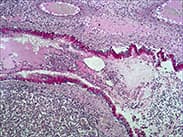

| 高碘酸-Schiff(Periodic acid SchiffPAS法) | 多糖、中性黏液物質(zhì)、酸性黏液物質(zhì) | 肝、腎、心肌、骨骼肌糖原累積癥;骨Ewing氏肉瘤和骨網(wǎng)織肉瘤鑒定 | ![]() |